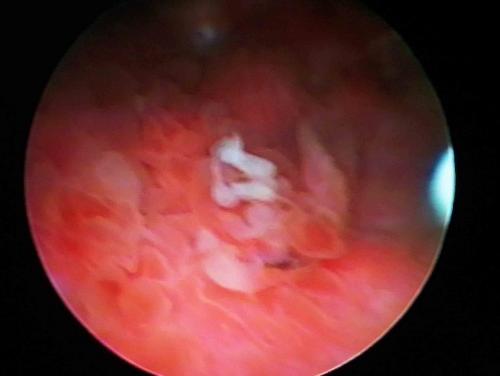

3.核基質蛋白22:針對于存在有膀胱癌的患者,核基質蛋白22水平可以升高為正常的80倍左右,提示可能存在膀胱腫瘤。1.診斷方法MRI可以針對膀胱癌的位置、大小和生長方式等進行立體無死角的診斷。

4.膀胱癌的MRI診斷表現主要包括:膀胱壁的增厚和不規則性——膀胱癌病變可導致膀胱壁增厚和不規則。對于高級別的膀胱癌,如鱗狀細胞癌和腺細胞癌等,治療難度較大,但仍有部分患者可以通過治療獲得較好的治療效果。

1.輔助診療MRI可以幫助醫生評估膀胱癌的生長方式、深度和侵犯范圍等,為手術的實施提供有力的輔助。膀胱癌術后需要定期復查,并遵從醫生的醫囑早期發現不良反應及疾病本身有無進展。